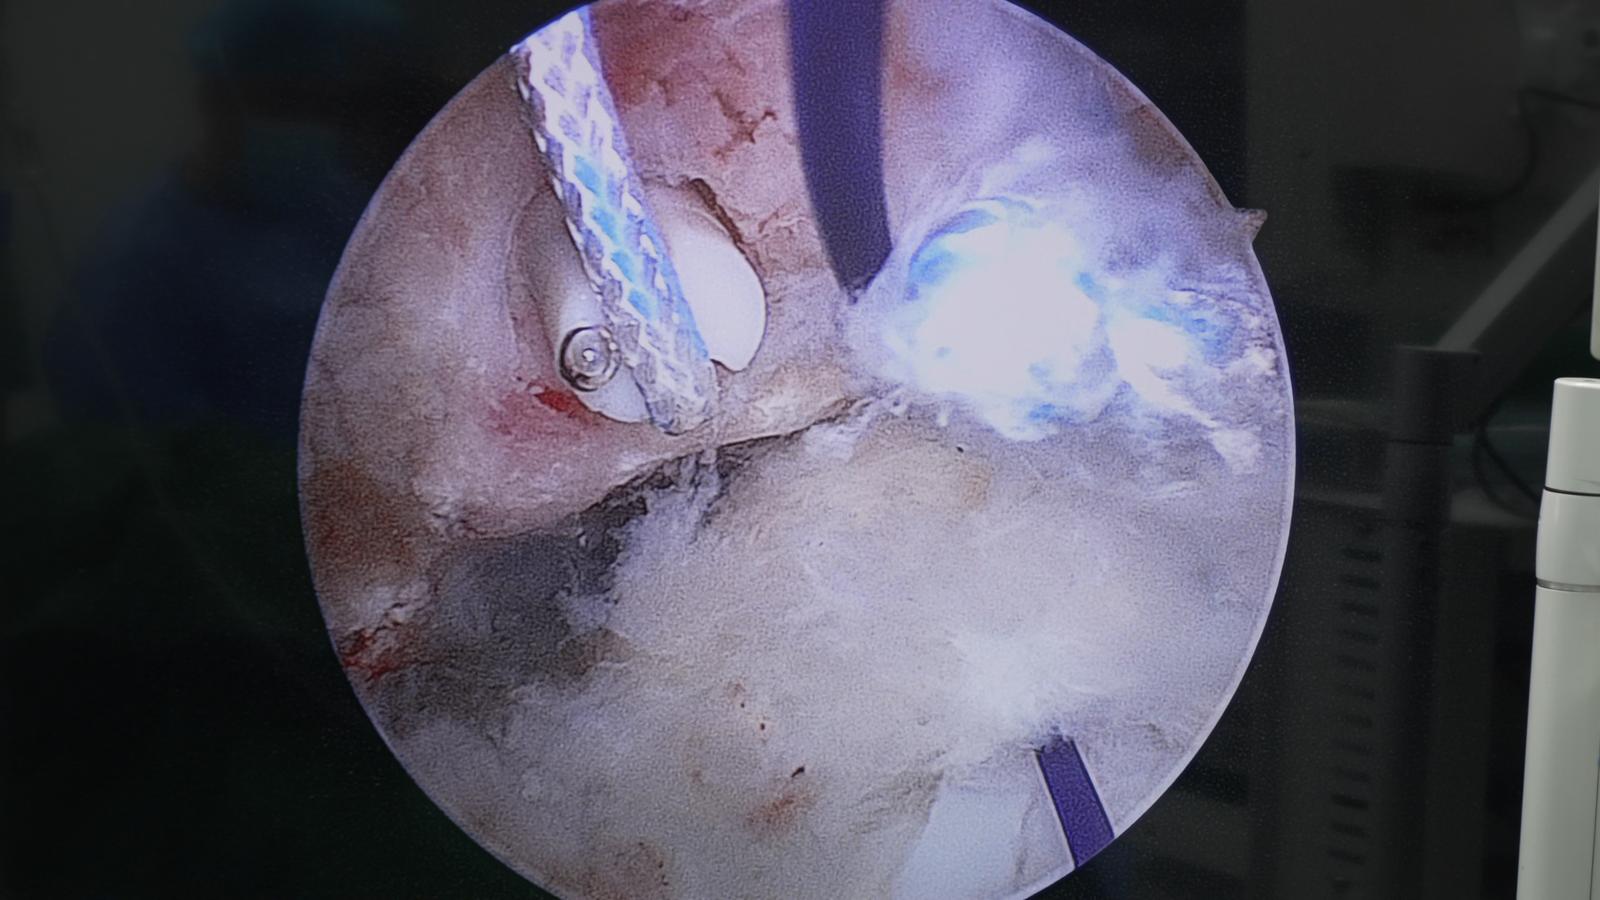

9月29日,手术顺利实施,李容镇博士为其完成“关节镜下滑膜切除术+盂唇缝合修补术+右髋臼骨赘切除术”。术后仅5天,王某梅的髋关节疼痛明显缓解,10月4日便康复出院。